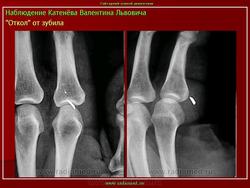

Инородные тела.

Приложения:

1.bit_.1.bit_.slayd57.jpg2.bit_.2.bit_.slayd58.jpg1.tr_.3.ino_.slayd36.jpg